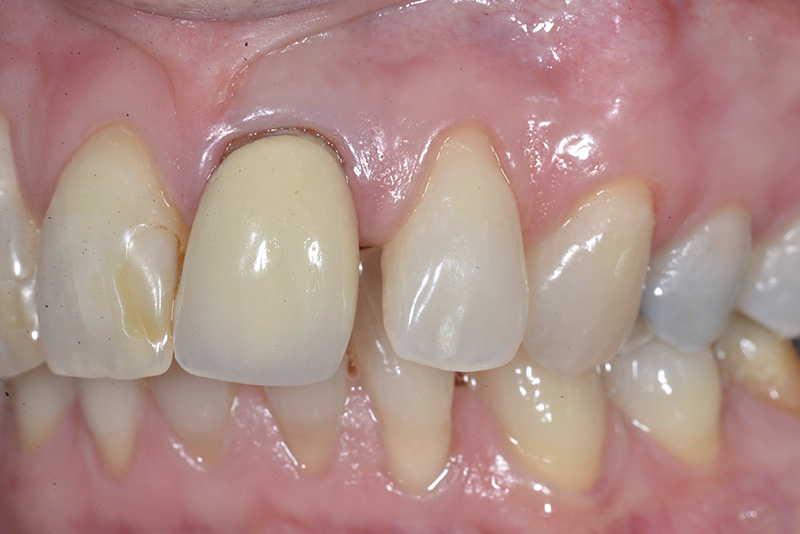

Vengono utilizzati 2 tipi di provvisori: il primo, cementato ai denti vicini, viene utilizzato dal momento dell’estrazione del dente fino ad impianto osteointegrato (circa 6 mesi); il secondo, avvitato direttamente all’impianto, ha una funzione di prova estetica ma soprattutto di guida per la maturazione dei tessuti gengivali peri-implantari portandoli verso la maturazione completa prima di posizionare la corona finale in disilicato di litio.